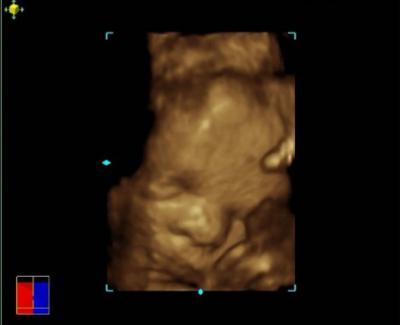

waren am donnerstag bei der vorsorge. 1500g, 29cm kopfumpfang und ca. 37-40cm groß. alles super, er meinte das sei ein deutsches durchschnittsbaby. auch nicht schlecht:-)) hier mal ein bild vom schmollmund und den blotschbäckchen, sieht geschissen aus wie der große bruder mit damals 2 wochen....

Bild zu unser deutsches durchschnittsbaby... - Forum für August - Mamis